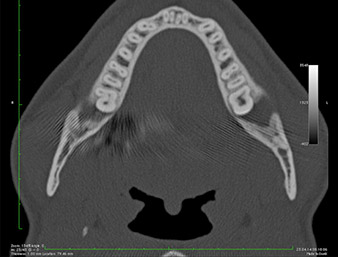

On voit sur l’image 3D (tomographie volumétrique numérique) que le reste radiculaire est en position disto-caudale au niveau de la transition de la partie horizontale vers la partie ascendante de la mandibule (Fig. 2).

Image DVT

Fig. 2 : Image DVT transversale du reste radiculaire dans la région rétromolaire.

Compte tenu de ses antécédents médicaux, notre patient (26 ans, non-fumeur) présentait de très bonnes chances

de réussite. L’OPG ayant révélé que le reste radiculaire était très proche du nerf alvéolaire inférieur, une tomographie volumétrique numérique a été effectuée en plus (6).